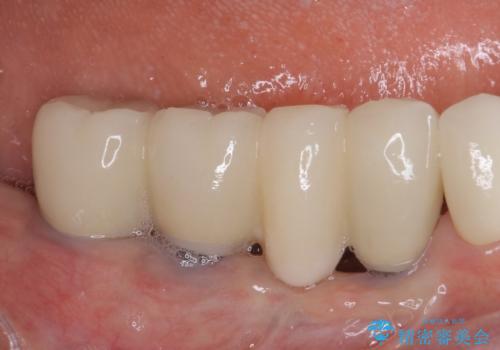

上下左右すべての奥歯に処置が必要であり、同時に行うと食事が取りにくくなってしまったり、手前の歯に負担がかかって初診時よりも状況が悪化したりする可能性があるため、片方ずつ処置を進めて行くこととしました。

下顎右側は骨造成を併用してインプラント治療を行い、その他の奥歯もインプラントや歯周外科処置を併用して補綴治療を進め、最後に前歯部の欠けてしまったセラミッククラウンを作り替えることとしました。